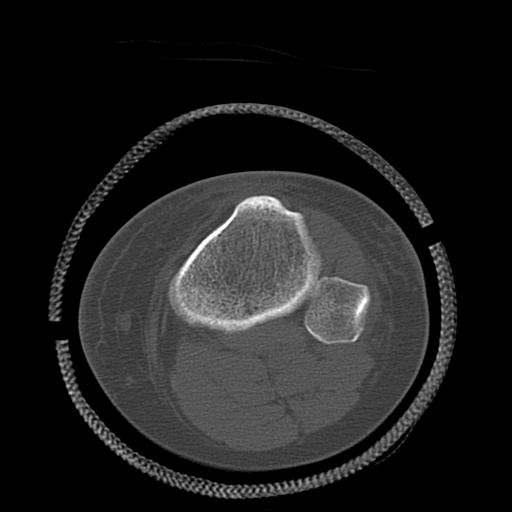

49554 3/13 膝 4R 3/16 4R 1/18 2R 78歳男性 膝蓋骨骨折